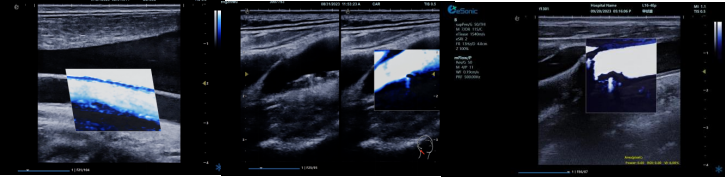

mFlowTM 超微血流显像技术

mFlowTM 超微血流技术在小型机器上率先实现微米级细小血管识别与低速血流捕捉,以往仅高端台式机具备此功能。该技术专注于颈动脉粥样硬化斑块内血流评估,无需造影剂,具有高分辨率、低运动伪像和高帧频成像特点。其优势如下:

image.png

? 运用 3D 壁滤波技术智能分析信号,可探测常规超声难以捕捉的低速血流,灵敏度高。

? 依据 Staub 标准对检查结果分级,直观展示斑块内新生血管血流,为斑块稳定性评估提供新指标。

? 基于多普勒原理,进行频谱测量并可进行VI指数测量,定量评估斑块内新生血管占比。

? 相较超声造影成像,无创便捷,为颈动脉易损斑块评估开辟新途径。